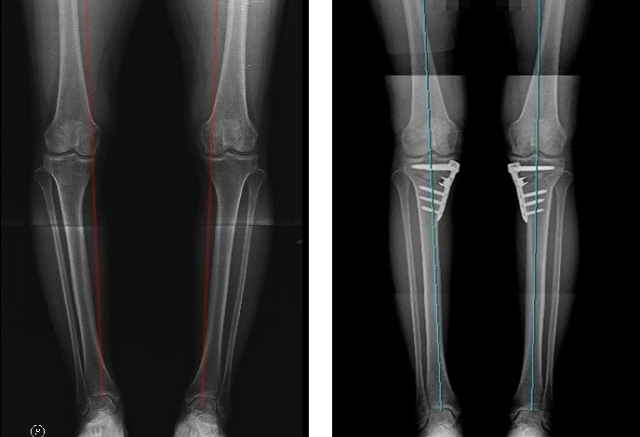

다리가 O자로 휜 다리는 고관절부터 발목으로 내려오는 체중선이 무릎 중심을 벗어나면서 안쪽 무릎으로 체중의 절반 이상이 집중돼 관절에 지속적인 부담이 가해진다. 이는 연골 마모 속도를 가속시키면서 내측 관절염을 유발하게 되고, 내측 연골만 비정상적으로 닳게 되면서 O자 변형을 더욱 가속화시킨다.

근위경골절골술은 O자로 휜 다리를 바르게 교정해 무릎 내측에 집중되어 있는 무게 중심을 고르게 분산시키는 교정술이다. 무릎 통증의 원인이 O자 변형이고, 내측 연골만 닳은 상태라면 근위경골절골술로 자신의 관절을 지키면서 관절염 진행을 막을 수 있다.

근위경골절골술은 인공관절수술과는 다르게 자기 관절을 보존하는 수술이므로 수술 후에도 정상 관절과 같이 관절 운동 범위에 제한이 없고 재활 후에는 등산과 같은 운동도 가능하기 때문에 비교적 젊은 나이의 관절염 환자들에게 각광받고 있다.